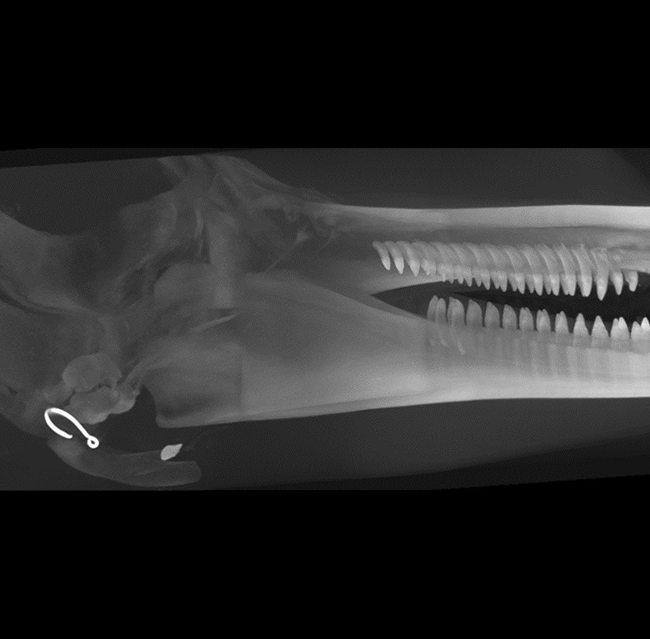

Our High Definition Volumetric Imaging (HDVI) technology is the most advanced form of Flat Panel CT technology. It delivers high-quality diagnostic imaging for both hard and soft tissues. This technology includes specific presets and customizable accessories designed for aquatic animals.

High Definition Volumetric Imaging (HDVI) Computed Tomography and Fluoroscopy in one device.

Outstanding image quality in hard and soft tissues with a spatial resolution up to 100 μ.